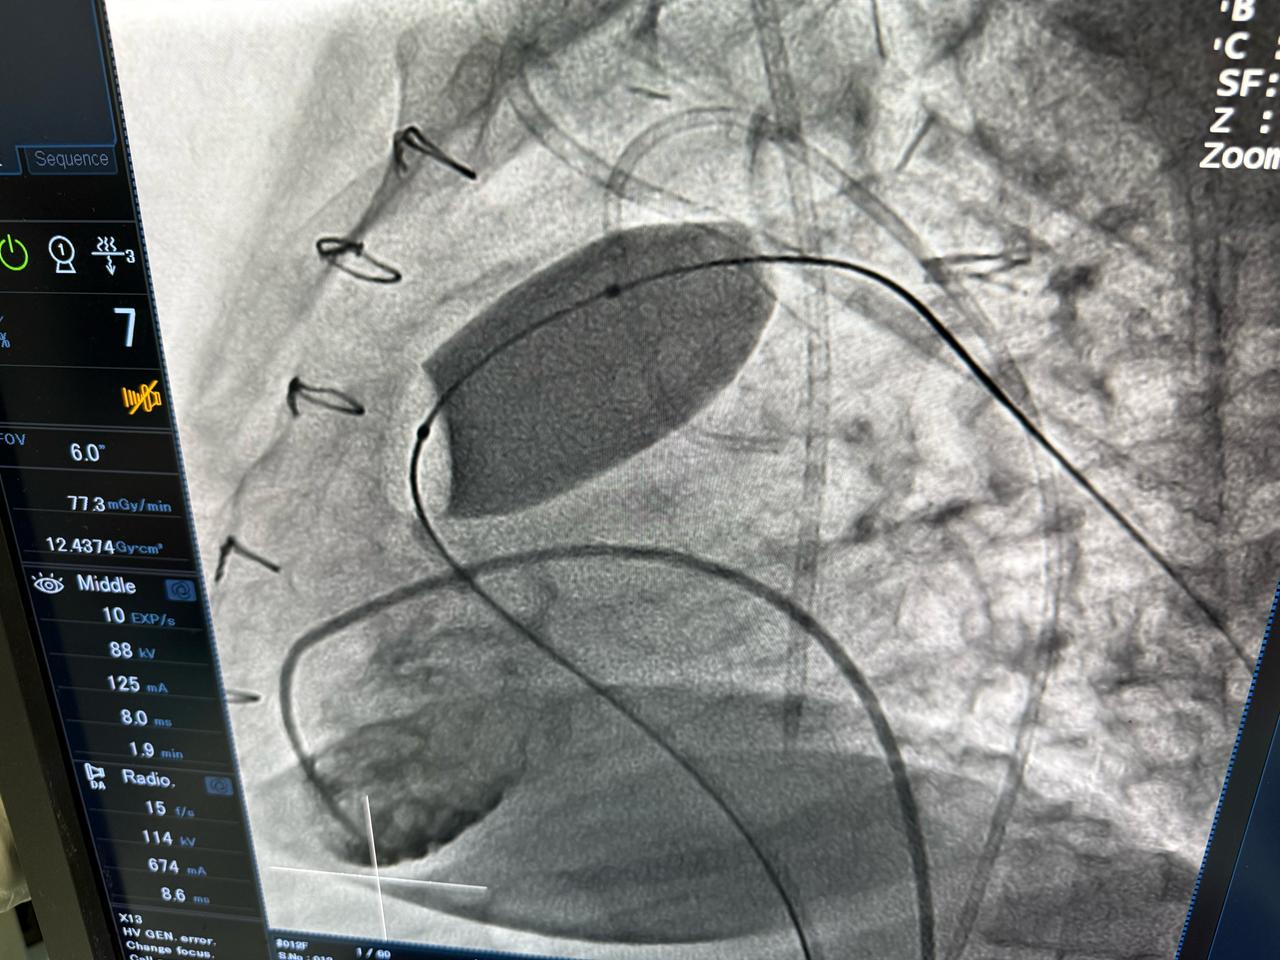

أعلنت وزارة الصحة والسكان عن نجاح عملية دقيقة لتغيير الصمام الرئوي بالقسطرة لشابة تبلغ من العمر 23 عامًا، كانت تعاني من ارتجاع شديد بالصمام الرئوي نتيجة جراحة رباعي فالوت السابقة، وهو أحد أكثر العيوب الخلقية القلبية تعقيدًا.

وصرّح الدكتور حسام عبد الغفار، المتحدث الرسمي لوزارة الصحة والسكان، بأن العملية أُجريت باستخدام أحدث التقنيات العالمية داخل أكاديمية قلب المبرة، التابعة للمؤسسة العلاجية، على يد نخبة من الخبراء المصريين، مؤكدًا أن هذا الإجراء الطبي المتقدم، الذي تجاوزت تكلفته مليون جنيه، يعكس قدرة الفرق الطبية المصرية على تنفيذ أدق التدخلات القلبية وفق أعلى المعايير الدولية.

وأضاف أن هذا الإنجاز يأتي ضمن جهود المؤسسة العلاجية لتوفير أحدث التقنيات الطبية للمرضى المصريين، حيث توفر مستشفى مبرة مصر القديمة مجموعة من الخدمات المتقدمة، من بينها تغيير الصمام الأورطي بالقسطرة (التافي) بمعدلات نجاح عالمية، وعلاج العيوب الخلقية للقلب بالقسطرة، وتوسيع الصمام الميترالي بالبالون، ما يعكس التطور الكبير في تقنيات علاج أمراض القلب داخل مصر.

وجرت العملية تحت إشراف الدكتور محمد إبراهيم شقوير، رئيس المؤسسة العلاجية، والدكتور هشام الفخراني، مدير مستشفى مبرة مصر القديمة، وبقيادة فريق طبي متخصص برئاسة الدكتور محمد صبري، رئيس قسم القلب، والدكتور أحمد السواح، مدير وحدة القسطرة، والدكتور علي جلال، مدير وحدة الأمراض الخلقية.